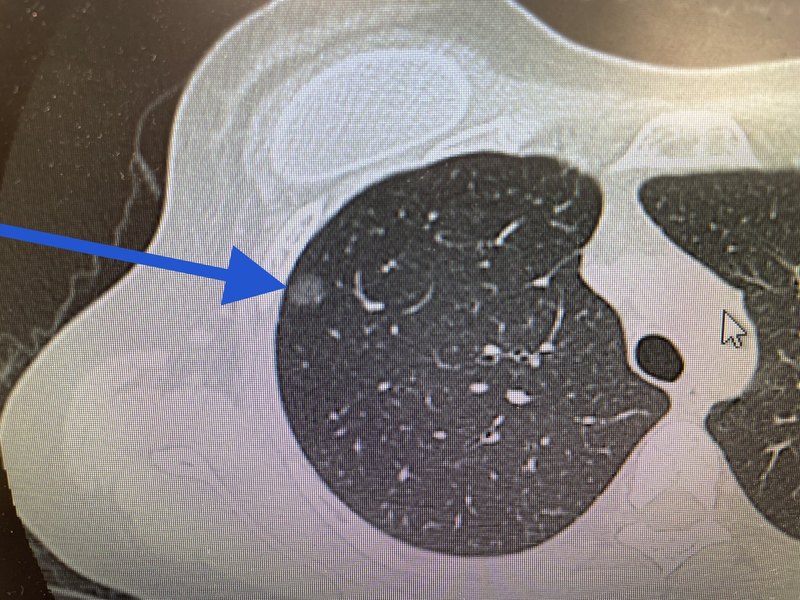

患者女性,四十多歲,從浙江來,性格非常開朗,住院期間每天笑呵呵,和醫(yī)生護士相處非常融洽?;颊?016年,因發(fā)現右下肺磨玻璃結節(jié)8mm,在上海某??漆t(yī)院做的右肺下葉切除手術,術后病理報告:微浸潤腺癌。術后第一個月CT復查,就發(fā)現了右肺上葉還有磨玻璃結節(jié),5mm。回過頭再對比術前CT,發(fā)現當時就有。醫(yī)生建議隨訪。在6年的隨訪過程中,右上肺磨玻璃結節(jié)慢慢在增大,今年長大到了10mm。因為是涉及到需要右肺的二次手術,而且以前是切了肺葉,醫(yī)生們都不太愿意接,建議做消融。也有醫(yī)生建議吃靶向藥,或者放療。經結友推薦找到了我們,經我院高分辨CT結合人工智能掃描,發(fā)現可不止一個結節(jié)。有三個結節(jié)。右上肺兩個,分別是10mm和4mm(圖1和2)。右中葉還有一個小混磨,5mm(圖3)。這次患者高度警惕了,也高度緊張了。要求一網打盡所有有危險的結節(jié),4mm的也一定要切,必須切,死活都要切。滿足了患者心愿,我們一網打盡了患者右余肺的3個磨玻璃結節(jié),都楔形切除小手術搞定。其實這些微小混合性磨玻璃結節(jié)不太好切的,主要難點在于結節(jié)太小,不好定位,術中很難找到。術中病理報告:結節(jié)1:微浸潤腺癌,結節(jié)2:原位腺癌,結節(jié)3(中葉小混磨,這個位置是中葉的小混磨,下葉已經沒有了):微浸潤腺癌。雖然是二次手術,但一網打盡了余下的所有有危險的結節(jié),病變都還是早早期的,也一樣治愈了。前天周五早上查房,問二次手術感覺和恢復得如何?患者的回復是:比6年前的手術,身體輕松10倍,心態(tài)好100倍(這是最高評價,雖然我知道有夸張成分)。因為患者年輕愛美,她的二次手術,我們利用的還是六年前的原切口,手術后也使用美容免拆線縫合,所以絕對找不到二次手術的切口。這樣的因多發(fā)磨玻璃結節(jié)漏診漏切而做的二次手術,幾乎每個月都有幾例,我們幾乎成了多發(fā)磨玻璃結節(jié)漏切的、二次手術專業(yè)戶,也讓我們摸索出二次手術的很多經驗和技巧。

上周末參加一朋友飯局,碰到重慶一知名學校校長。席間聽說我是有名的肺結節(jié)專家,很得意的講了他去年發(fā)現肺結節(jié)準備手術,后免挨一刀的故事。話里話外,戲談我們這些“專家”。他說:他去年發(fā)現右上肺9mm磨玻璃結節(jié),隨訪三個月后入住我市知名三甲醫(yī)院準備手術。他的一個該院醫(yī)生朋友,全國排名前三的介入診斷專家去看他。說不著急做啊,我給你穿刺一下再說,很簡單的。穿刺病理報告:肺泡塌陷,慢性炎。見如下圖1。后面省略1000字。我淡淡的回復:校長,您先別太武斷,我的感覺就不對。要不明天就到我們醫(yī)院復查高分辨率CT,我只有眼見為實,才能給您一個精準的回應。可能氣場給了他壓力,第二天,也就是本周一,他真到了我門診復查了CT。結節(jié)如下圖2。因為已穿刺過的原因,結節(jié)已非常不好判斷,形似一個大蝌蚪,后面一個長長的尾巴。我的建議還是4個字:惡性,手術。本周五手術的。術中病理報告,見圖3和圖4:微浸潤腺癌,完全符合預判。圖4紗布上:左側是結節(jié),結節(jié)旁邊的箭頭所指是穿刺針道條索狀的東西。都送大病理檢查,不知道針道有沒有種植轉移。這個案例還是成就感爆棚,主要有兩個點:1救人一命,因為病人已完全相信穿刺病理,這個惡性結節(jié)不知道要發(fā)展到哪個程度才能再引起患者的警惕,很可能就耽誤了。而這個時候手術,微浸潤腺癌階段,根治率可接近100%,不需要任何后續(xù)治療。2明明穿刺病理是良性的,復查CT影像也模糊了。僅僅憑眼睛,要推翻病理診斷,建議手術,需要特大特大特大的勇氣。如果手術真開出來的是肺泡塌陷和慢性炎癥,這個朋友沒法做了,而且這位朋友更會,話里話外戲談我們這些“專家”好久好久了。